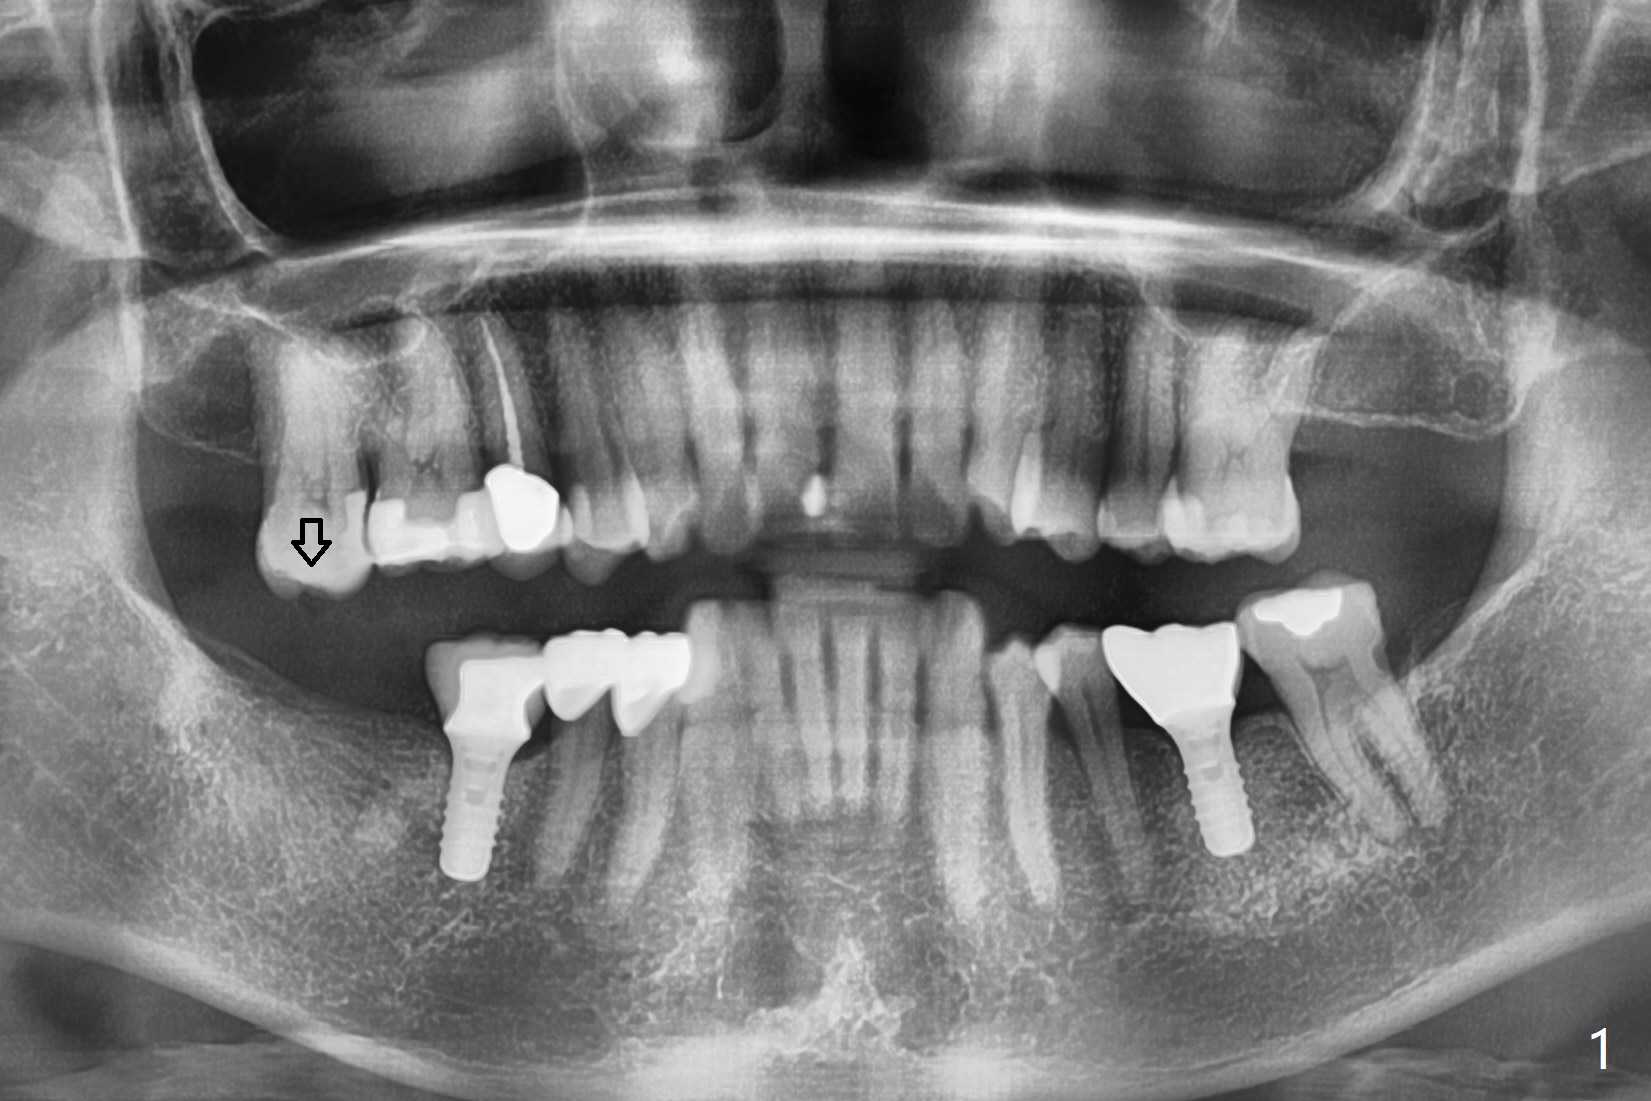

61岁女同意先做右下7植牙,可能困难是对合牙过度萌出(图一:箭头),还好对合牙牙尖比较长,有余地磨除。虽然牙槽骨很宽(图二),但是牙槽嵴顶(图三:>)缺乏皮质骨,密度很低(图四)。所以钻头必须小(4毫米),不必攻螺纹。